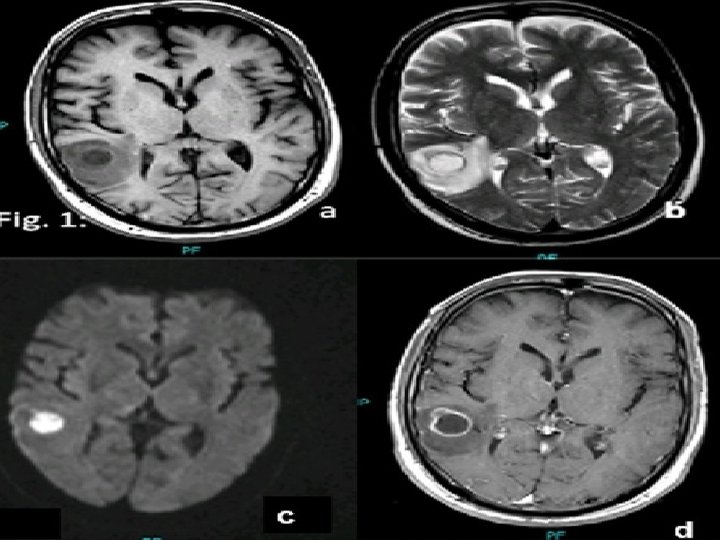

INVESTIGATIONS Radiological characteristic of brain abscess 1. Brain CT with contrast Ring enhancement Sigle Locus/Multi loculation Multiplicity Finding of gas

MRI T 1 : necrotic center ( hypointense) Capsule ( hyperintense) Edema ( hypointense) T 2 : necrotic center ( hyperintense) Capsule ( hypointense) Edema ( hyperintense)